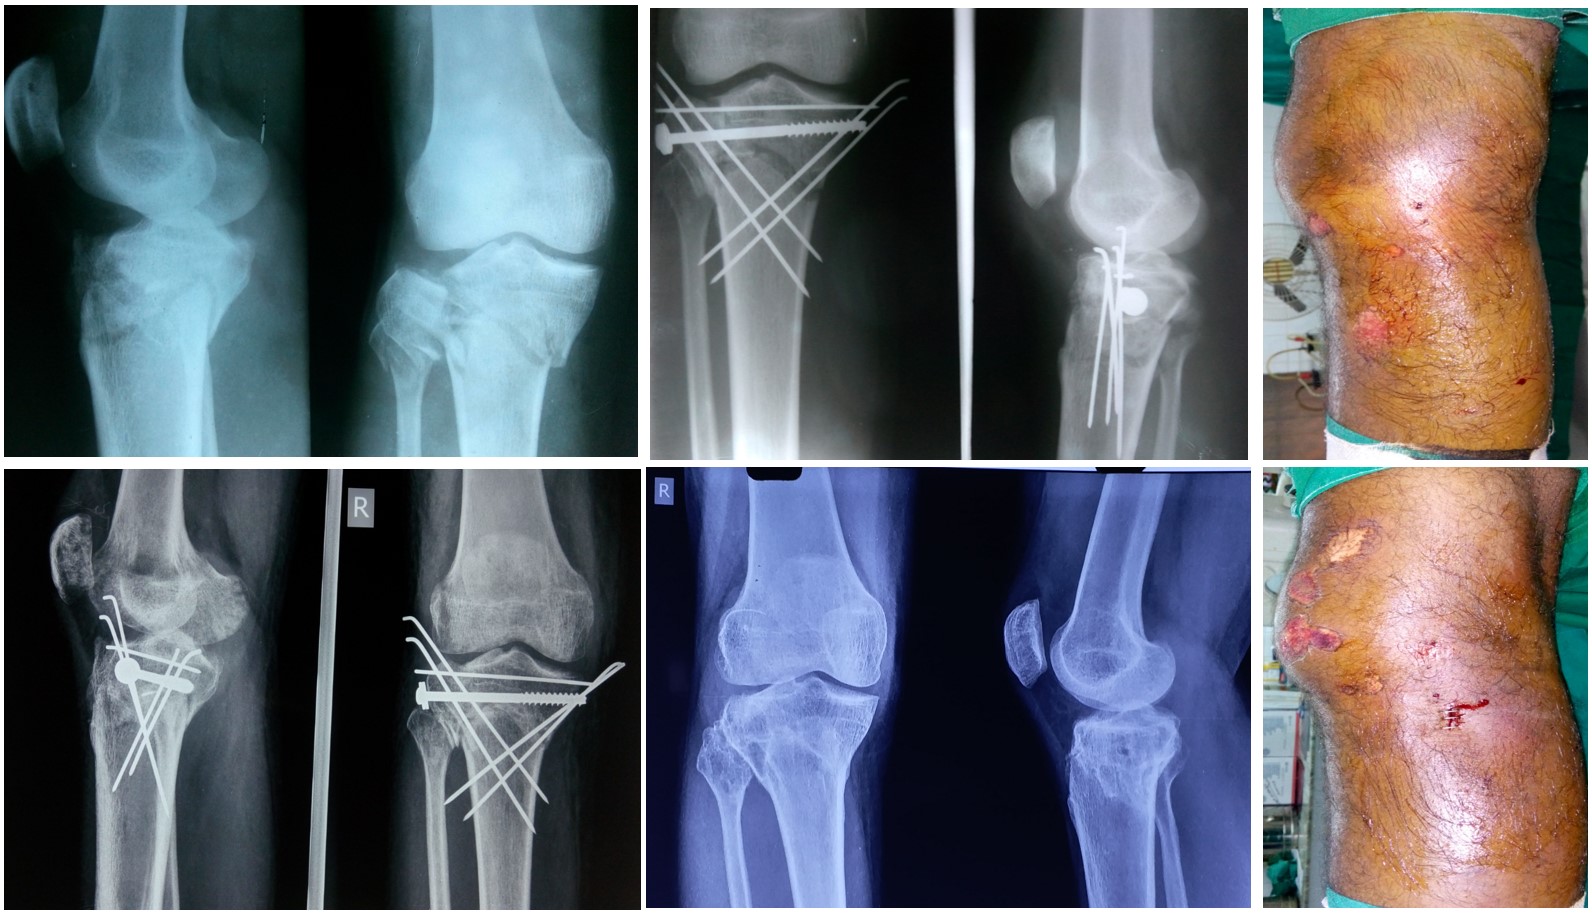

Proximal 3rd Leg